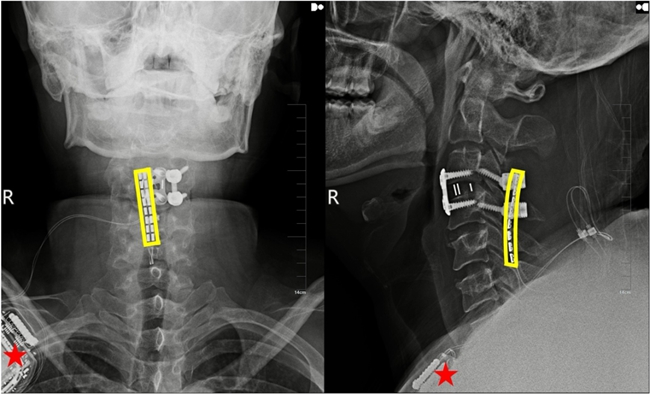

植入術后X線顯示,黃色方框為電極位置,星號為皮下脈沖發射器位置。

術后確認患者狀態平穩后,治療團隊開始進行損傷脊髓的電刺激治療?;颊呓邮艹绦蚧姶碳H6小時,即能在電刺激輔助下實現下肢肌肉收縮。接受電刺激2周后,患者已能自主完成抬腿、屈膝等動作。目前患者已逐步恢復雙側膝關節屈伸、右側手指抓握等關鍵功能,腳趾活動度顯著提升,實現了從“癱瘓在床”到“對抗重力運動”的跨越。